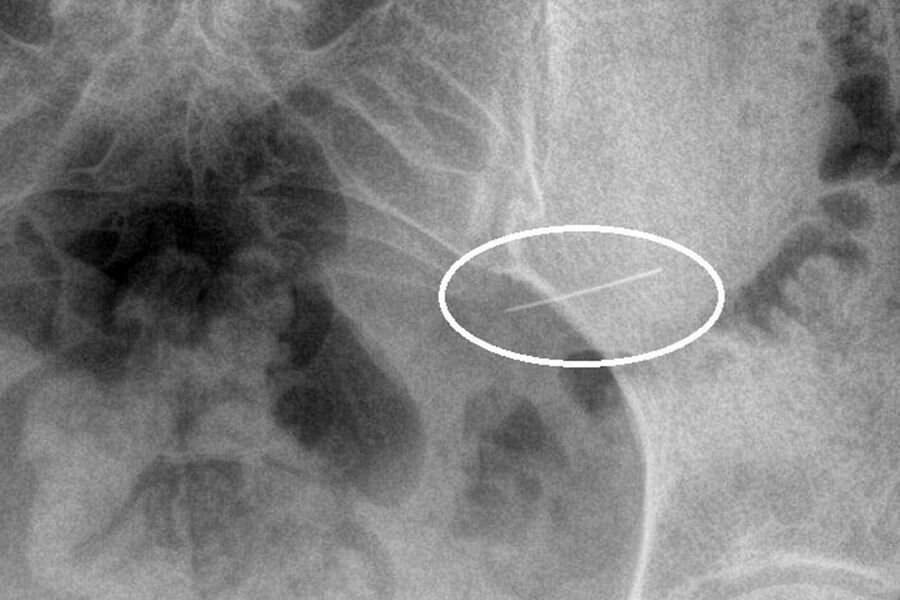

Пациентка вовремя обратилась за помощью, и бригада скорой доставила ее в стационар. Рентген брюшной полости показал инородное тело в желудке. Врачи первого хирургического отделения подготовили ее к экстренной операции, после чего с помощью современного оборудования эндоскописты аккуратно удалили опасный предмет, не допустив осложнений.